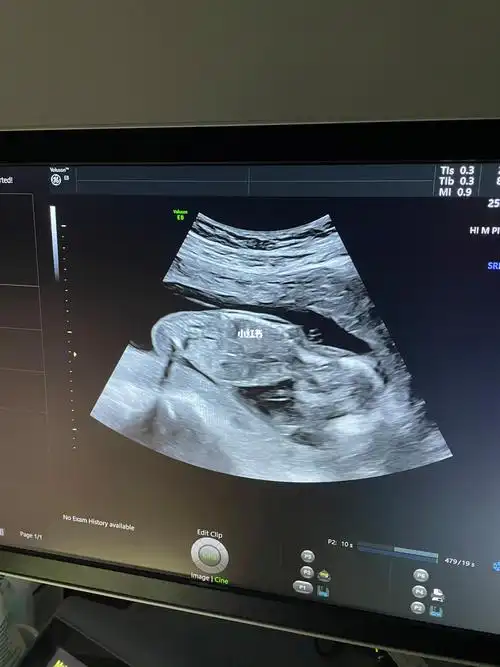

图片还没什么感觉,b超室里看到动态的样子,老母亲真的很激动!

孕16周的胎儿有多大?宝妈应该注意些什么?育儿妈妈来支招